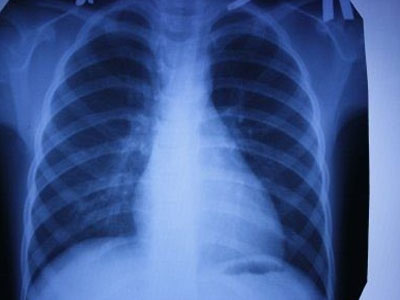

据我国大的出国看病服务机构厚朴方舟了解,日本科学家近日宣布,他们成功发现了一类基因,它们的变化具有加速人类肺癌细胞扩散的可能性。

科学家在非吸烟者身上诊断出了这一疾病类型。这类基因一共有六种。日本癌症研究中心的专家在研究中得出了这一结论。他们对1.8万余人的医疗数据进行研究,研究参与者中既有健康人群,也有癌症患者。

专家指出,这些基因主要在发现机体受感染时起到免疫反应。破坏这些基因的工作会导致癌细胞加速增长。基因变化会提高20%的癌症发病率,在有些情况下会提高40%的癌症发病率。

据科学家称,这些基因特性的发现有助于在早期阶段确定人类身上的肺癌病理学,这对于癌症能否及时治疗至关重要。